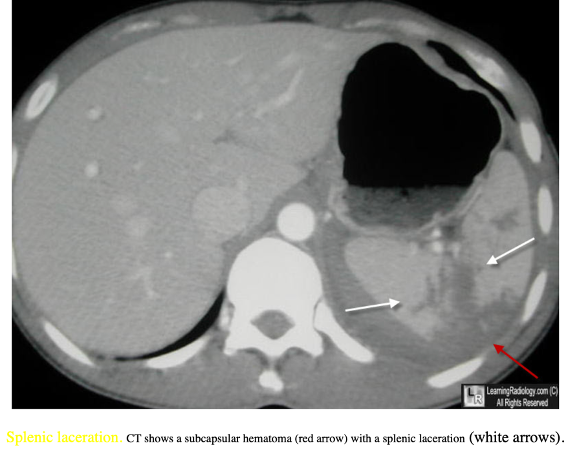

Miltraume:

20

Q

Diagnose?